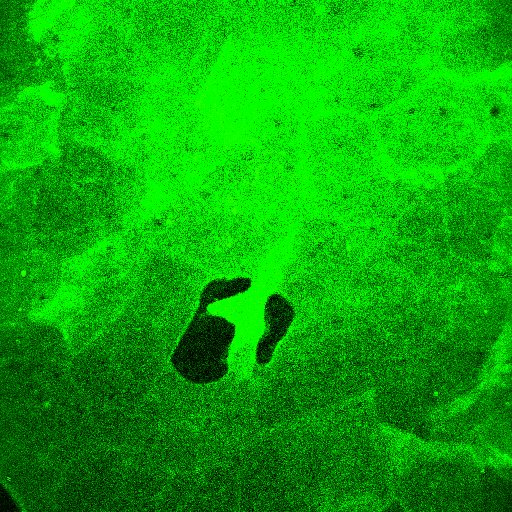

2.微针创伤检测

利用医美微针压刺手臂皮肤之后,用双光子检测微针创口。

图9. 角质层存在明显的不规则创口,网状纤维层对应位置出现无信号区,说明微针刺穿了基底层

(以上双光子图源来自CIRS化妆品功效临床评价实验室)